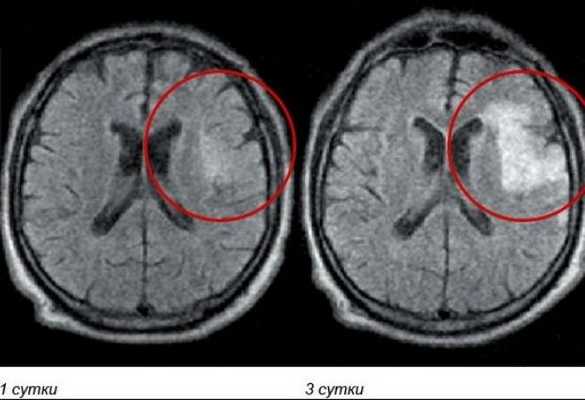

Красным выделен участок ишемии мозга в динамике на МРТ

- лейкоареоз — изменение белого вещества вокруг желудочков головного мозга (на рисунке 1, белое свечение вокруг желудочков);

- лекоэнцефалопатия — поражение белого вещества головного мозга (на рисунке 1 и 3, светлые участки в подкорковом веществе);

- малые инфаркты, ишемические инсульты (рисунок 3);

- множественные микрокровоизлияния (рисунок 2 — темные участки);

- атрофия коры головного мозга.

Существует зависимость между типом и выраженностью морфологических изменений мозгового вещества и стадией заболевания [4] [6] .